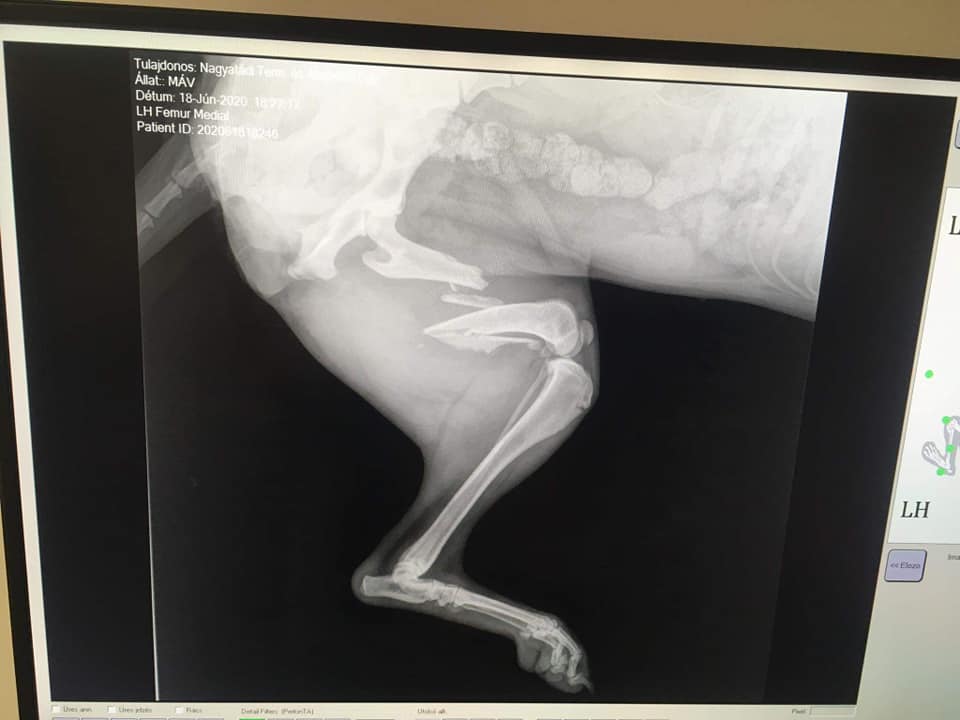

Eine weitere sehr traurige Nachricht erreichte uns aus Ungarn. (Nagyatád) Vor 2 Tagen wurde die kleine Máv von einem Zug erfasst. Ihr wurden dadurch beide Beine gebrochen. Die junge Hündin lag 2 Tage zwischen den Gleisen, man dachte, sie sei tod.

Doch Máv lebte, schwer verletzt und mit grossen Schmerzen. Sie musste so schlimme Ängste aushalten! Täglich rauschten mehrere Züge an ihr vorbei und sie konnte sich selber nicht davon bewegen. Sie ist nun in unserer Obhut und einige Operationen werden nötig sein, um die kleine Seele zu retten.